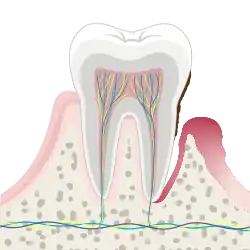

Teeth before (top) and after (bottom) a thorough mechanical debridement | |

In dentistry, debridement refers to the removal by dental cleaning of accumulations of plaque and calculus (tartar) in order to maintain dental health.[1] Debridement may be performed using ultrasonic instruments, which fracture the calculus, thereby facilitating its removal, as well as hand tools, including periodontal scaler and curettes, or through the use of chemicals such as hydrogen peroxide.

Dental debridement is a procedure by which plaque and calculus (tartar) that have accumulated on the teeth is removed.[1] Debridement may be performed in the process of personal or professional teeth cleaning. Professional debridement techniques include the use of ultrasonic instruments (which fracture the calculus, thereby facilitating its removal), as well as the use of hand tools, including periodontal scaler and curettes. Debridement may also be performed using saline solution.